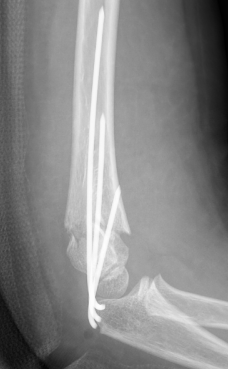

此种类型的骨折称为肱骨髁上骨折,在完善相关辅助检查后予行麻醉下平乐郭氏手法正骨经皮钢针内固定治疗,术后患儿恢复良好,手术部位只有几个小针眼。(下图为患儿术后X线片)